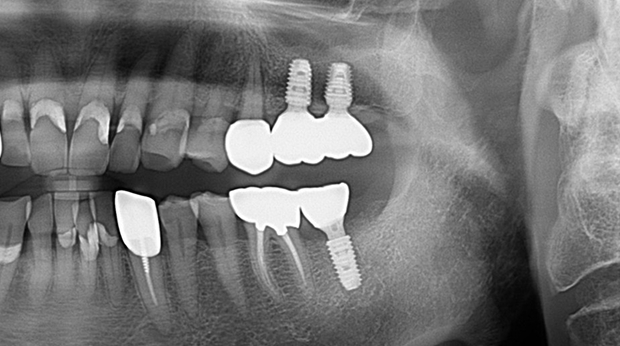

고난도 수술 진료

임플란트와 사랑니 발치는 외과적 시술로 잇몸을 절개하는 외과적 시술은

짧으면 짧을 수록 시술 후 붓기와 통증이 최소화됩니다.

치과의사 경력 14년차 구강외과 전문의가 빠르고 안전하게, 아프지 않게 수술해 드립니다.

치과경력 14년차 구강외과 전문의

연세대학교 치과대학 구강외과 임상 조교수